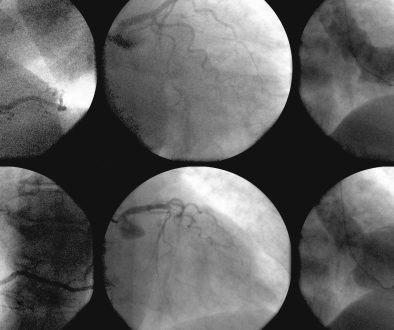

1. **القسطرة البالونية**

تعد القسطرة البالونية إجراءً شائعًا يعتمد على إدخال بالون صغير عبر القسطرة إلى الصمام المتضيق، ثم نفخه لتوسيع الصمام. هذه الطريقة تُعتبر بشكل عام أقل توغلاً من الجراحة التقليدية، وتستخدم بشكل خاص للمرضى الذين لا يتحملون الجراحة المفتوحة.

3. **استبدال الصمام عبر القسطرة (TAVR)**

هذا الإجراء هو خيار متاح للمصابين بضيق الشريان الأورطي ويعتمد على إدخال صمام بديل عبر القسطرة دون الحاجة إلى جراحة مفتوحة.